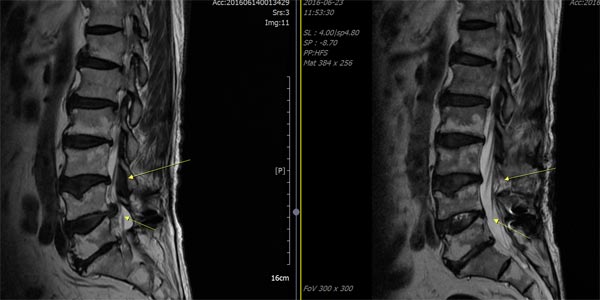

척추관협착증 수술 전(좌측)과 수술 후(우측) MRI 사진. 눌려있던 신경이 펴진 것을 확인할 수 있다/서울바른세상병원 제공